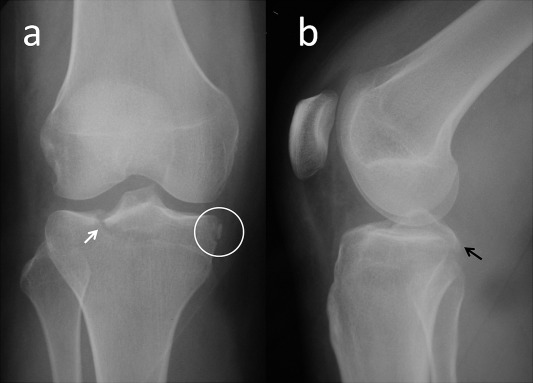

Under spinal anesthesia and tourniquet control, physical examination followed by standard diagnostic knee arthroscopy was performed at the second day. During arthroscopy, the ACL was found edematous but it was intact and pivot shift test was negative. There was grade I medial laxity indicating MCL injury. Both menisci were found intact with arthroscopic examination. There was no cartilage lesion in femoral condyles. The avulsion fracture of the PCL was extending to the lateral tibial plateau, PCL was found to be lax with probing. After the diagnostic arthroscopy, the patient was turned to prone position, and S shaped incision was made over the popliteal fossa. A meticulous dissection was made down to the posterior capsule with sparing medial and lateral head of gastrocnemius muscle. The capsule was cut longitudinally and the fracture fragment was exposed. Under fluoroscopic control, the fragment was temporarily fixed with two Kirschner wires and two headless cannulated compression screws were used to fix the fracture (Fig. 3 ). The postoperative period was uneventful. Patient wore a knee brace and active knee range of motion exercises was started and gradually increased without weight bearing during the first 6 weeks. At the 6th week weight bearing was allowed. At the final follow-up 18 months after the initial injury, the patient was free of pain and returned to her previous level of activity and work. Final knee radiographs showed the union of PCL avulsion fracture (Fig. 4 ). Knee range of motion was normal (between 0 and 130°) and painless. Anterior drawer test, Lachman test, posterior drawer test and medial and lateral stress tests were all negative. There was no ligamentous laxity or instability. Meniscus examination test including joint line tenderness, McMurray and Apley tests were negative both for medial and lateral menisci. Lysholm Knee Score was 100 points and rated as excellent.

Fig. 4

Fig. 4.

Final anteroposterior (a) and lateral (b) knee radiographs showing complete union of fractures at post-operative 18th month.